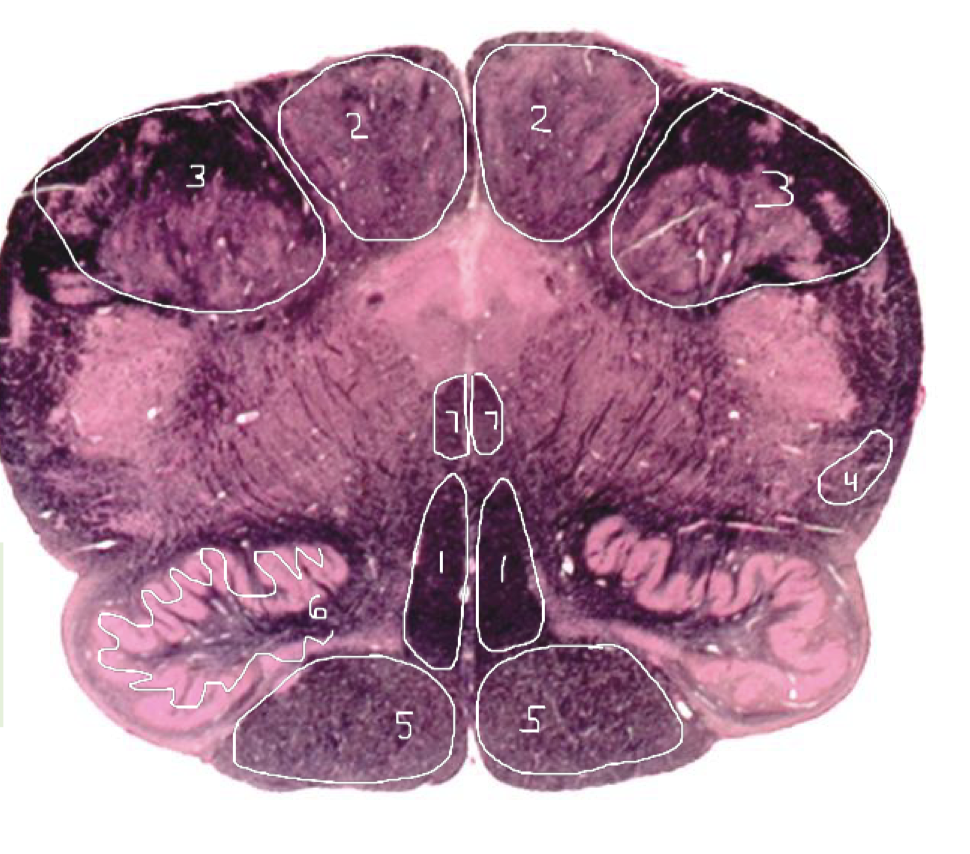

1

Medial Lemniscus - Caudal Pons

2

Spinothalamic Tract - Caudal Pons

3

CST - Caudal Pons

4

4th Ventricle - Caudal Pons

5

Inferior Cerebellar Peduncle - Caudal Pons

6

Middle Cerebellar Peduncle - Caudal Pons

7

Superior Cerebellar Peduncle - Caudal Pons

8

Dentate Nuclei (Cerebellum) - Caudal Pons

9

Inferior Olivary Nucleus - Caudal Pons

10

Medial Longitudinal Fasciculus (MLF) - Caudal Pons